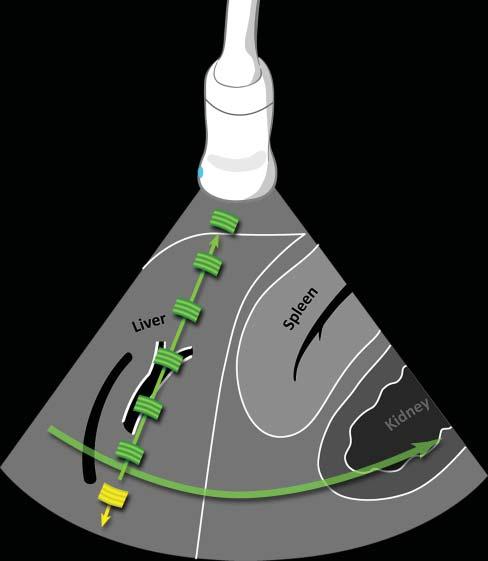

Toproducean image,thefirstpiezoelectriccrystals arestimulatedtogenerateashortultrasoundpulse–comprisingthreetofourwaves–thattravelsthrough tissueinterfacestoproducethousandsofechoes thataresentbacktotheprobe(Figure1.1).Shortly

afterward,anewultrasoundpulseleavestheprobe atadifferentangle,generatinganewsetofechoes thatreturntothesecondseriesofcrystals.Assuminga constantwavepropagationspeedof1,540m/sinsoft tissues,eachoftheseechoescanbelocatedprecisely alongthetrajectory,dependingonthetimeinterval betweenthedepartingwaveandthereturningecho (Hangiandreouetal.2003).Hundredsofwavelinesare producedthisway,scanningtissuesathighspeedto produceover30images/s,eachonecontainingthousandsofpixelsdescribingtheacousticcharacteristics ofthescannedtissues.

Figure1.1. Ultrasoundpropagationandimageformation. Eachultrasoundimageisformedbytheadditionofhundredsofindividualscanlines.Eachlineisproducedaftera singleultrasoundpulse(inyellow)isemittedbythetransducer.Asthispulsepropagatesthroughsofttissues,many echoes(ingreen)aregeneratedatinterfacesofdifferentacousticimpedance(suchashepatocytes–connectivetissue),producinganimageofvariableechogenicityandechotexture. Eachechoisanatomicallylocalizedbasedonthetimeinterval betweentheemittedpulseanditsreception.Afteraspecific time,anewpulseisemittedalonganadjacentline,producing anadditionalscanline.Scanlinesaregeneratedveryrapidly andsuccessively,producing15–60images/s,allowing“real time”ultrasonography.